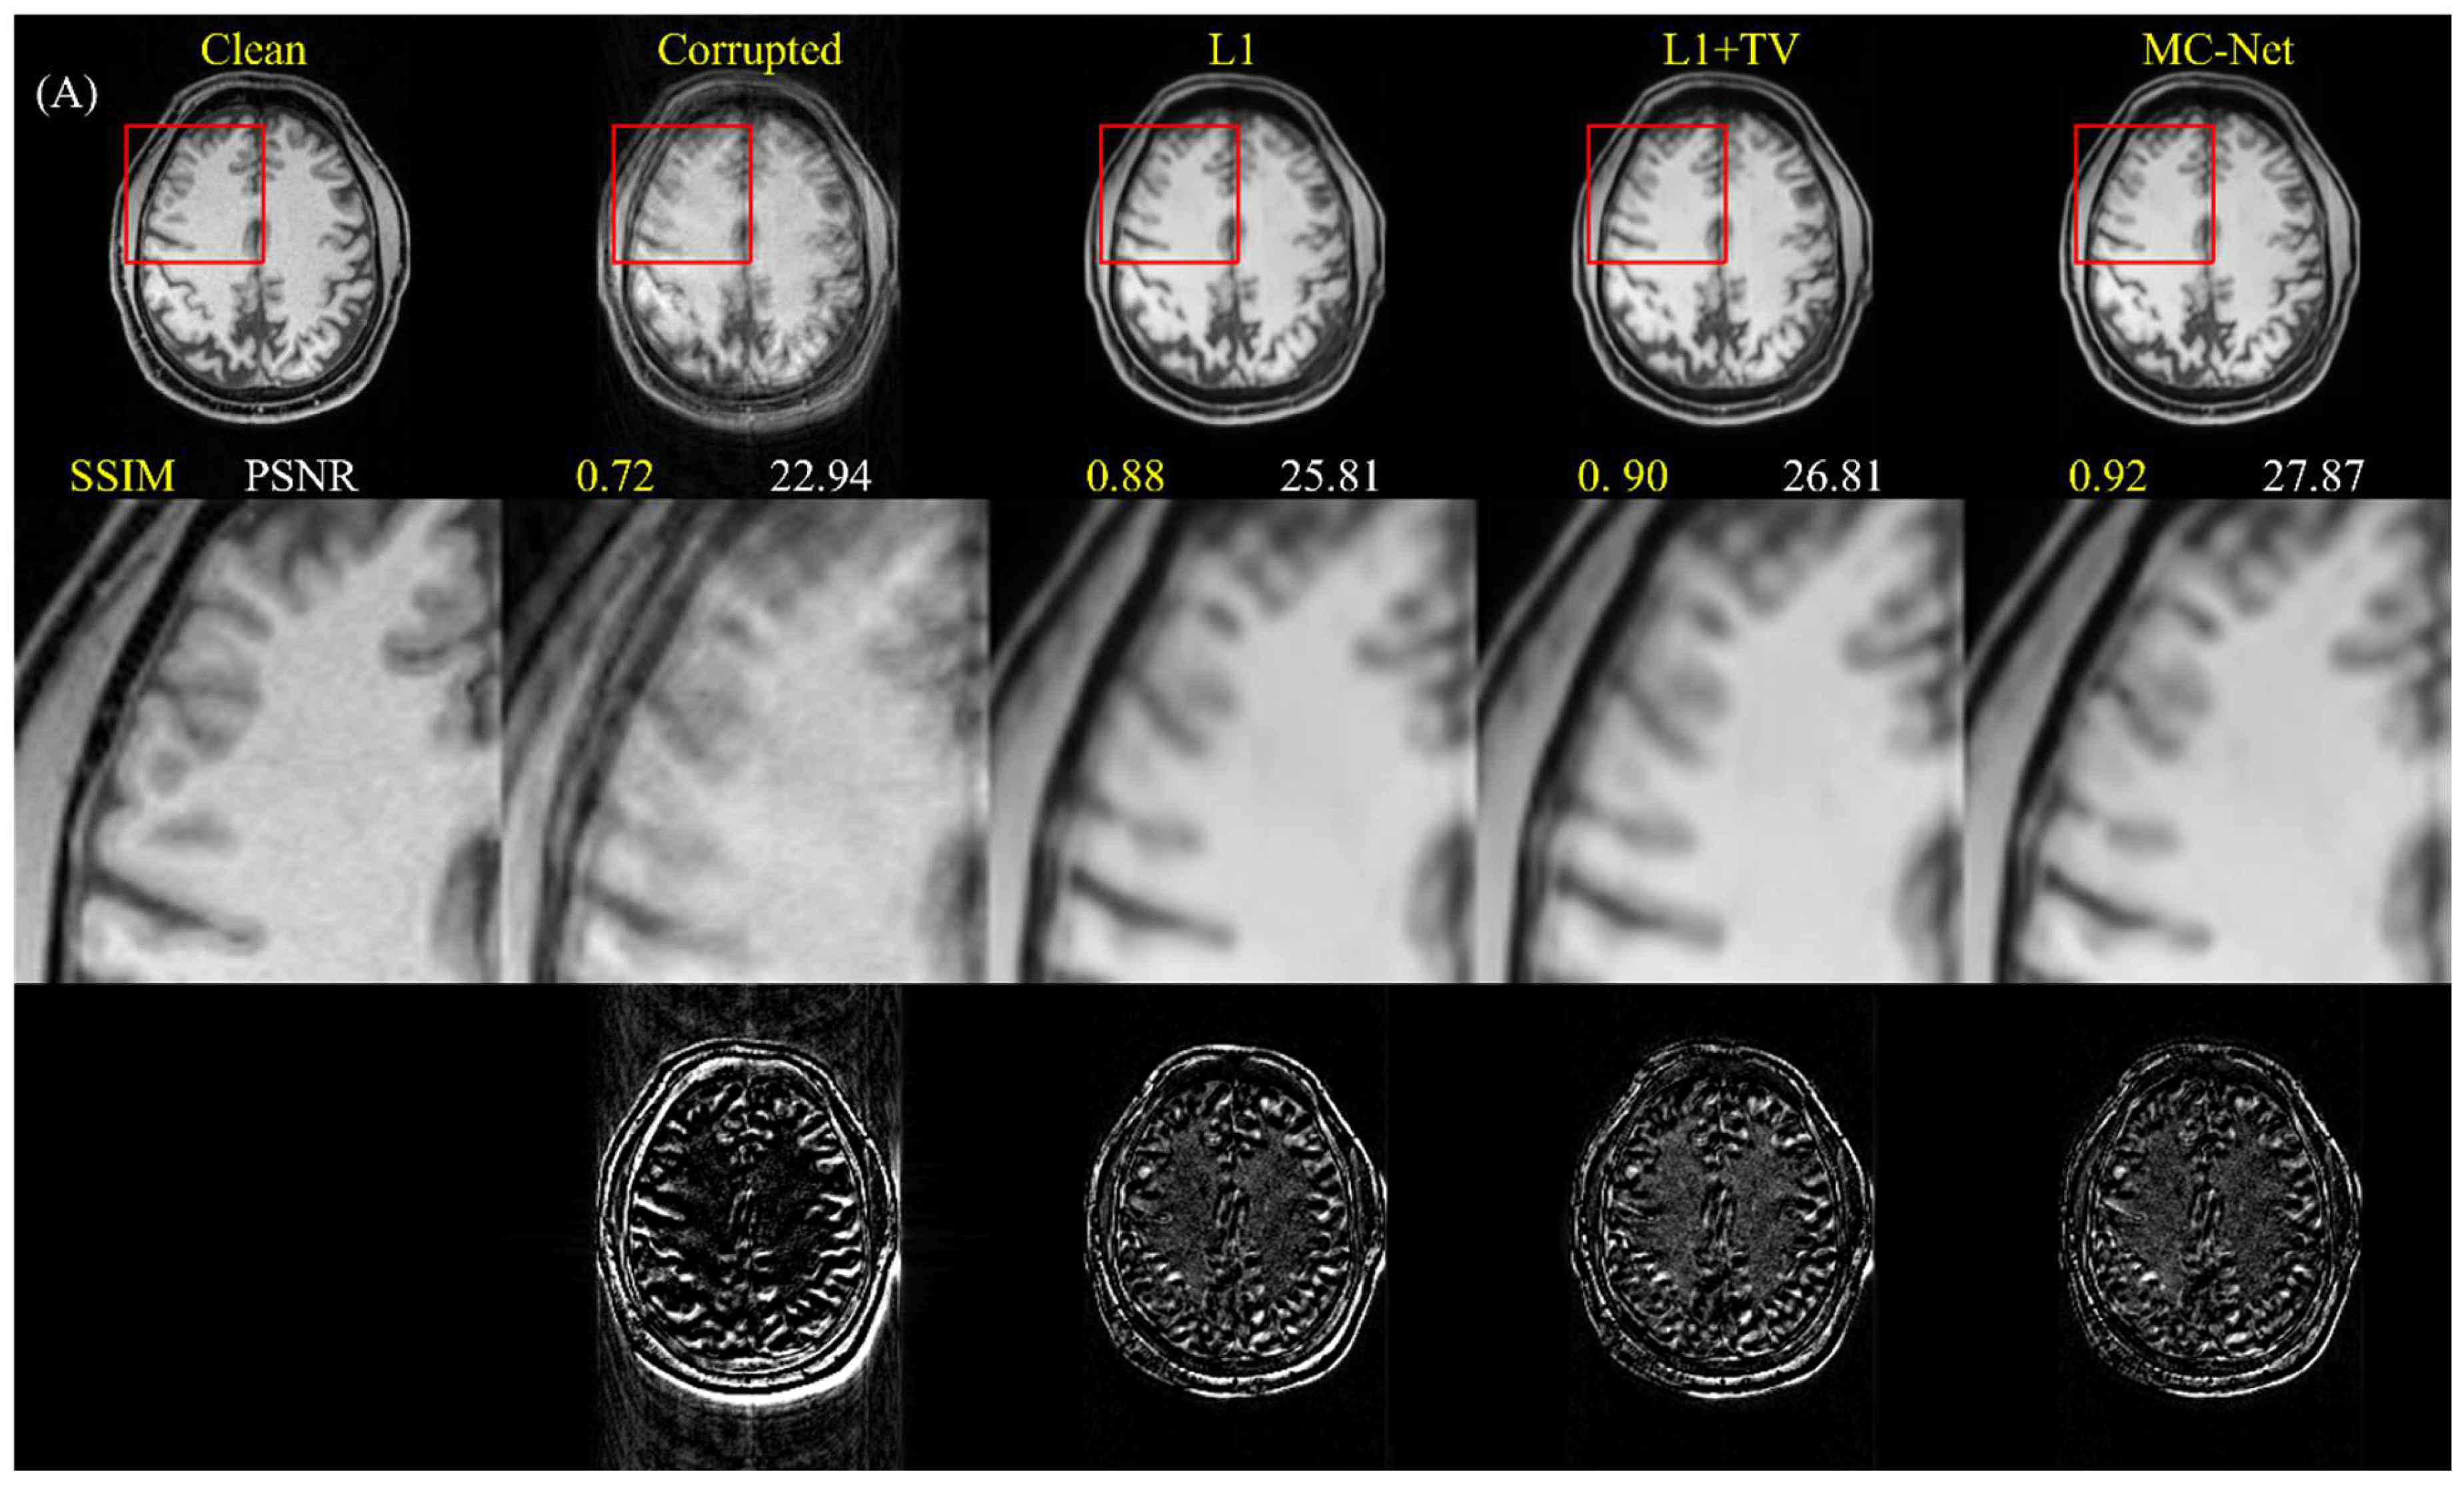

4.1. Quantitative Improvements for Motion-Corrupted Images

5.1. Advantages of Two-Stage Training and Multiple-Loss Function

| Model | Corrupted | L1 | L1 + TV | Two-Stage | |

|---|---|---|---|---|---|

| SSIM | U | 0.773 ± 0.099 | 0.908 ± 0.036 | 0.910 ± 0.036 | 0.919 ± 0.033 |

| PSNR | U | 26.346 ± 3.315 | 29.005 ± 2.736 | 29.077 ± 2.713 | 29.717 ± 2.736 |

| SSIM | U + O | 0.773 ± 0.099 | 0.811 ± 0.078 | 0.811 ± 0.078 | 0.816 ± 0.077 |

| PSNR | U + O | 26.346 ± 3.315 | 26.938 ± 3.224 | 26.844 ± 3.216 | 27.056 ± 3.276 |